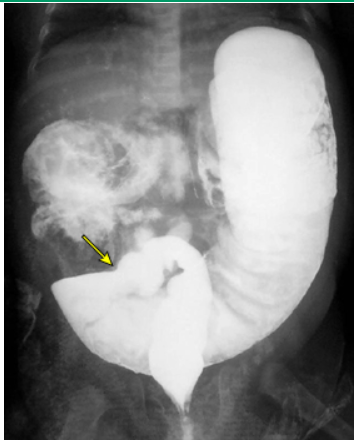

Como pode ser feito o dx da doença de Hirchsprung?

O procedimento de escolha é a bx retal 2 cm acima da linha denteada. Outros: manometria anorretal com pressão se mantendo ou elevando, radiografia abdominal contrastada com zona de transição entre a região acometida e a poupada.